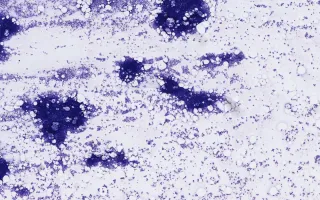

Bone Marrow, Acute myeloid leukemia, aspirate

70 year-old woman with new onset of pancytopenia, fever, weight loss, and generalized fatigue, previously healthy.

In this case, the bone marrow biopsy shows increased granulopoiesis and megakaryopoiesis. CD34 highlights 40-50% of blasts. The bone marrow aspirate is hypercellular with multilineage dysplasia in the form of dysplastic granulocytes and megakaryocytes. The flow cytometric pattern is also consistent with AML as the blasts express C13/33/34/117/38/71 and HLA-DR. MPO is positive. B and T cell markers are negative. The cytogenetic study shows monosomy 7. Monosomy 7 is sufficient for a diagnosis of AML with myelodysplasia-related changes according to the WHO 2008 classification in the absence of prior cytotoxic therapy. In the setting of AML, monosomy is associated with a relatively poor prognosis.

This slide shows the bone marrow aspirate. See Related Content for H&E & CD34 stains of the bone marrow biopsy.